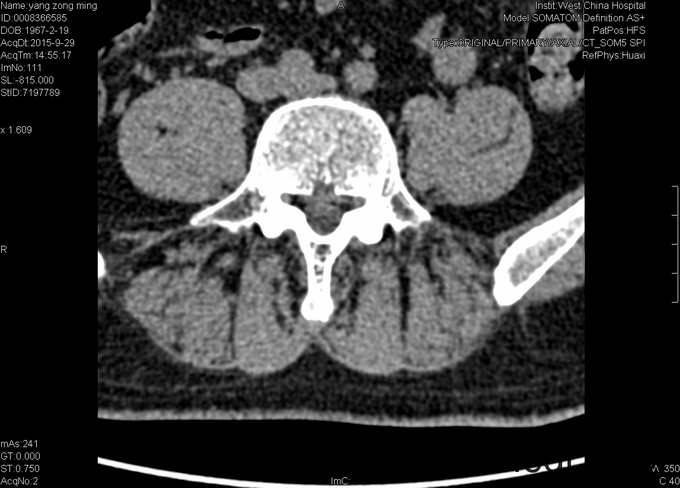

专科情况:视:双下肢等长,皮肤黏膜完整,无破损,双下肢肌肉无萎缩,脊柱外形正常。触:腰5-骶1棘突间压痛,腰部VAS疼痛评分5分,右下肢VAS疼痛评分6分,右下肢针刺觉减退。动量:四肢肌力、肌张力正常。右侧直腿抬高试验(+),加强实验(+),加强实验(-),双侧髌骨研磨试验(-)。生理反射均正常引出,病理征阴性。辅助检查:2015-9-29数字化X光腰骶椎正侧位摄影示:腰骶退行性病变、骨质疏松。数字化X光胸部正侧位摄影示:心肺未见明显异常。CT椎体一个部位骨三维成像扫描示:1、腰椎退行性病变,L5/S1椎间盘稍向右后突出2、骶管囊肿。MRI腰椎普通扫描示:1、L5/S1椎间盘突出2、腰椎退行性病变。

初步诊断:1、腰5骶1椎间盘突出症;2、骶管囊肿;3、骨质疏松。经皮内镜右侧椎间孔入路腰5骶1椎管减压+椎间盘髓核摘除+射频成形术